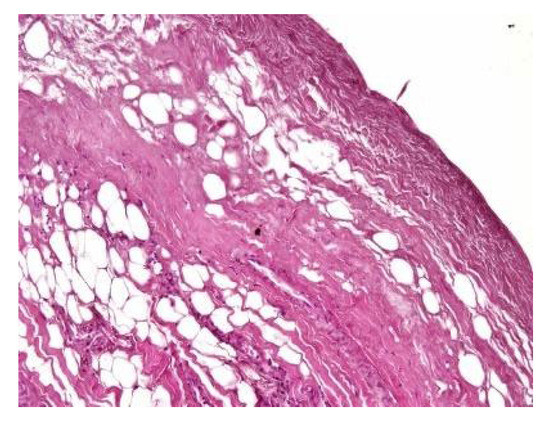

In both of the described cases, optical microscopy revealed lamellar fibrosis, deposits of fibrin on the surface of the peritoneum (Figure 3 and Figure 4) and dystrophic calcifications in the peritoneum (Figure 5 and Figure 6).

Figure 5. Dystrophic calcifications in the peritoneum (hematoxylin and eosin staining, original magnification × 100).

Jcm 13 02921 g005

Figure 6. Dystrophic calcifications in the peritoneum (hematoxylin and eosin staining, original magnification × 100).